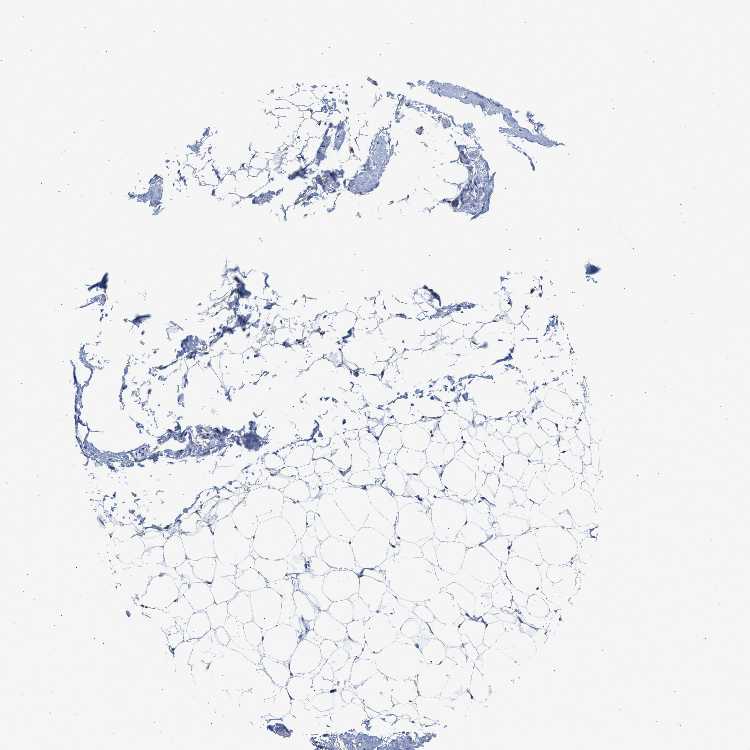

SOFT TISSUE 2 - Antibody stainingi

Antibody staining in the annotated cell types in the current human tissue is reported as not detected, low, medium, or high, based on conventional immunohistochemistry profiling in selected tissues. This score is based on the combination of the staining intensity and fraction of stained cells.

Each image is clickable and will lead to virtual microscopy that enables deeper exploration of all samples and also displays staining intensity scores, fraction scores and subcellular localization as well as patient and tissue information for each sample.

Antibody HPA021165Antibody HPA021753Antibody HPA021760

Fibroblasts Not detectedNot detectedNot detected

Peripheral nerve Not detected-Not detected